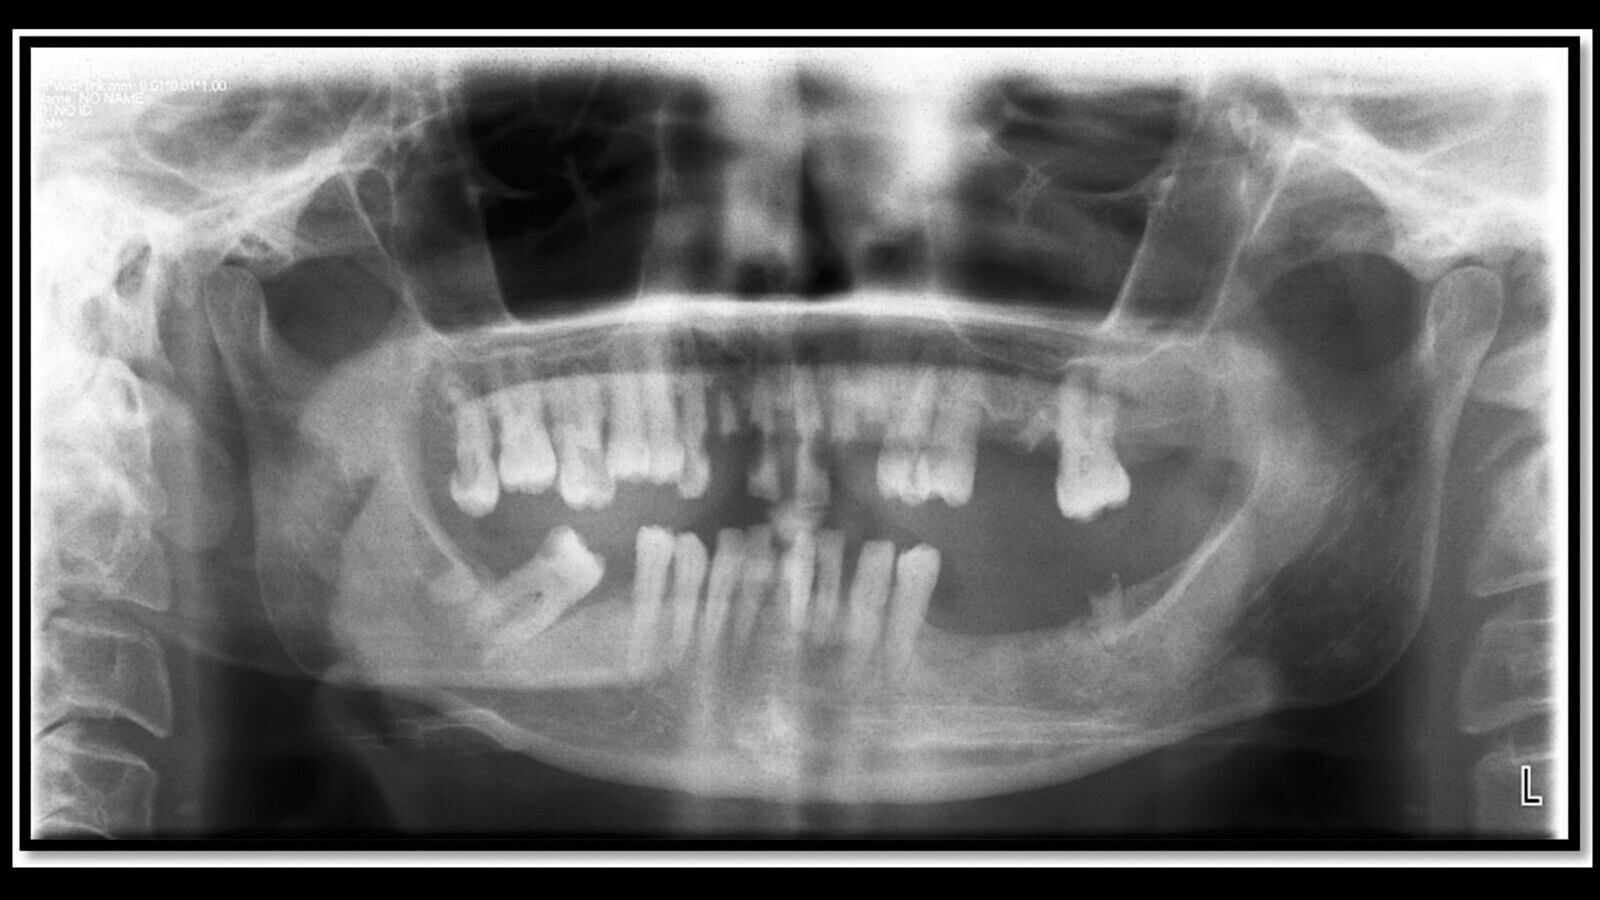

En la primera situación, se debe de hacer una historia clínica exhaustiva, una correcta exploración oral y radiografías (aletas de mordida, periapicales y panorámicas). Tendremos un tiempo de 15-21 días antes del inicio del tratamiento oncoterápico, en el cual se deben realizar las exodoncias simples, siempre dejando 15 días al inicio de la terapia (si las exodoncias son complejas, éstas deben de realizarse al menos 21 días antes).

2. b) Mal estado bucal (higiene pobre, enfermedad periodontal grave, y más de 20 caries) (Figura 1).

Figura 1. Paciente de 60 años, en mal estado de salud oral, y en tratamiento con tamoxifeno. En estos pacientes puede ser aconsejable realizar una edentación total.

1. c) Estado bucal regular (no enfermedad periodontal grave, menos de 20 caries e higiene regular) (Figura 2).

Figura 2. Paciente de 66 años de edad, en estado de salud oral aceptable, y en tratamiento con tamoxifeno. Se debe concienciar al paciente sobre higiene oral, hacer aplicación de flúor y tratamiento conservador de aquellos dientes que puedan ser restaurables.

1. d) Estado bucal bueno (Figura 3) (no enfermedad periodontal, caries casi ausentes y buena higiene).

Figura 3. Paciente de 65 años de edad, en buen estado de salud oral, con antecedentes de cáncer de colón tratado a los 61 años. Se debe concienciar al paciente sobre higiene oral, hacer aplicación de flúor y tratamiento conservador de aquellos dientes que puedan ser restaurables, cirugía preprotésica y periodontal, eliminar prótesis metálicas si se va a recibir radioterapia.

En pacientes con mal estado bucal procede realizar una edentación total. Si tiene un estado bucodental aceptable o bueno se debe concienciar al paciente sobre higiene oral, hacer aplicación de flúor, tratamiento conservador de aquellos dientes que puedan ser restaurables, cirugía preprotésica y periodontal, eliminar prótesis metálicas si se va a recibir radioterapia y toma de impresiones y fabricación de modelos de estudio por si hiciera falta más adelante.